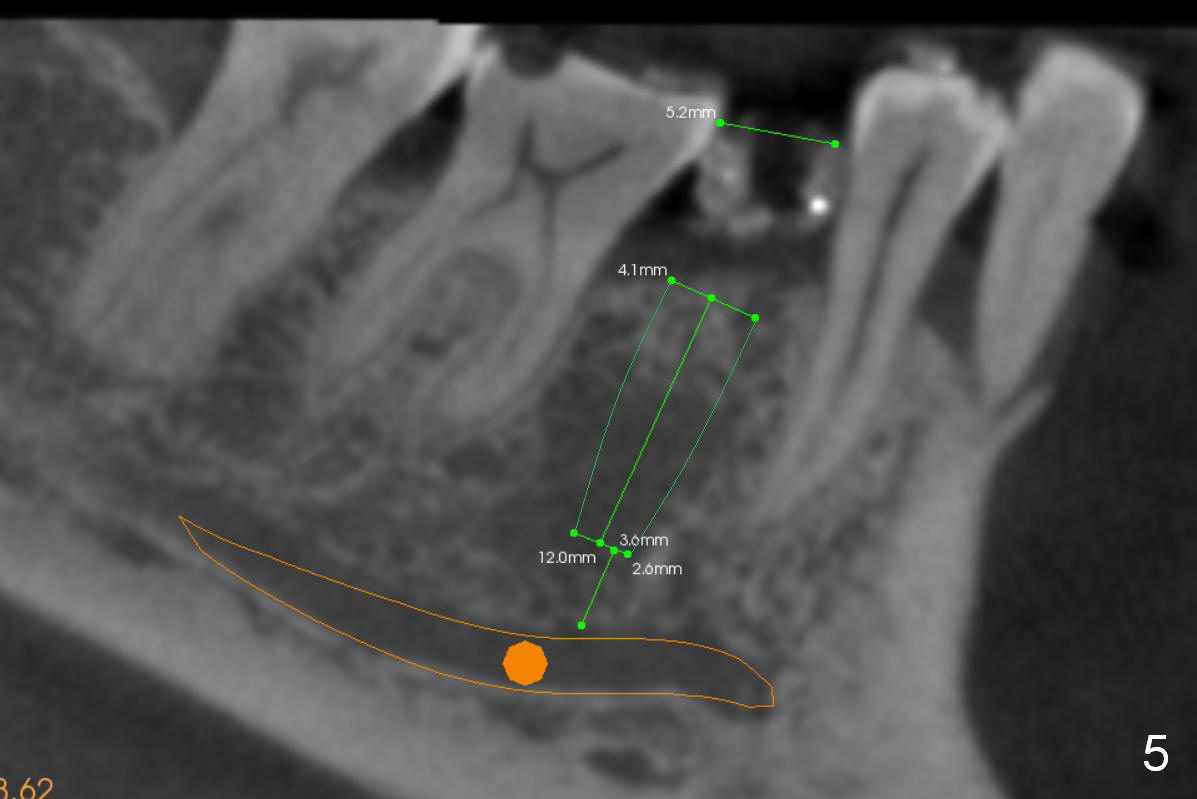

The first implant will be placed at #29 (Fig.4,5). The pointed ridge will be flattened to start osteotomy (Fig.6,7 (surgical handpiece)). The buccolingual dimension of the flattened ridge should be ~ 6 mm. The initial depth will be 12 mm. Take the 1st PA. A restorative high speed handpiece may be needed to remove the enamel of the mesial surface of #30 and the distal surface of #28 to increase space for implant placement.